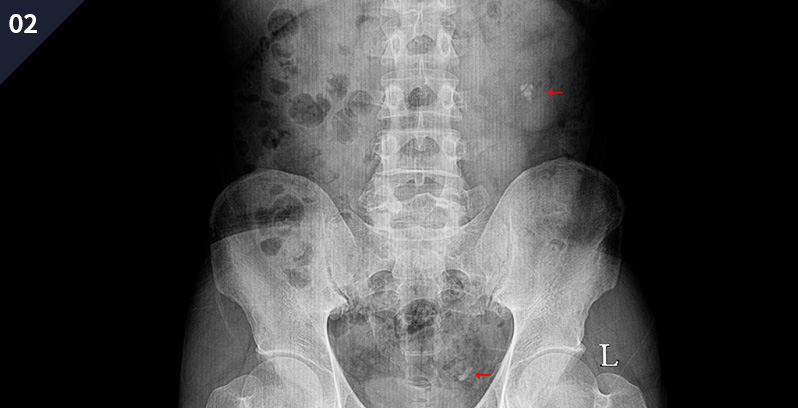

이러한 경우 의심 가능하다!

요 로 결 석 증 상